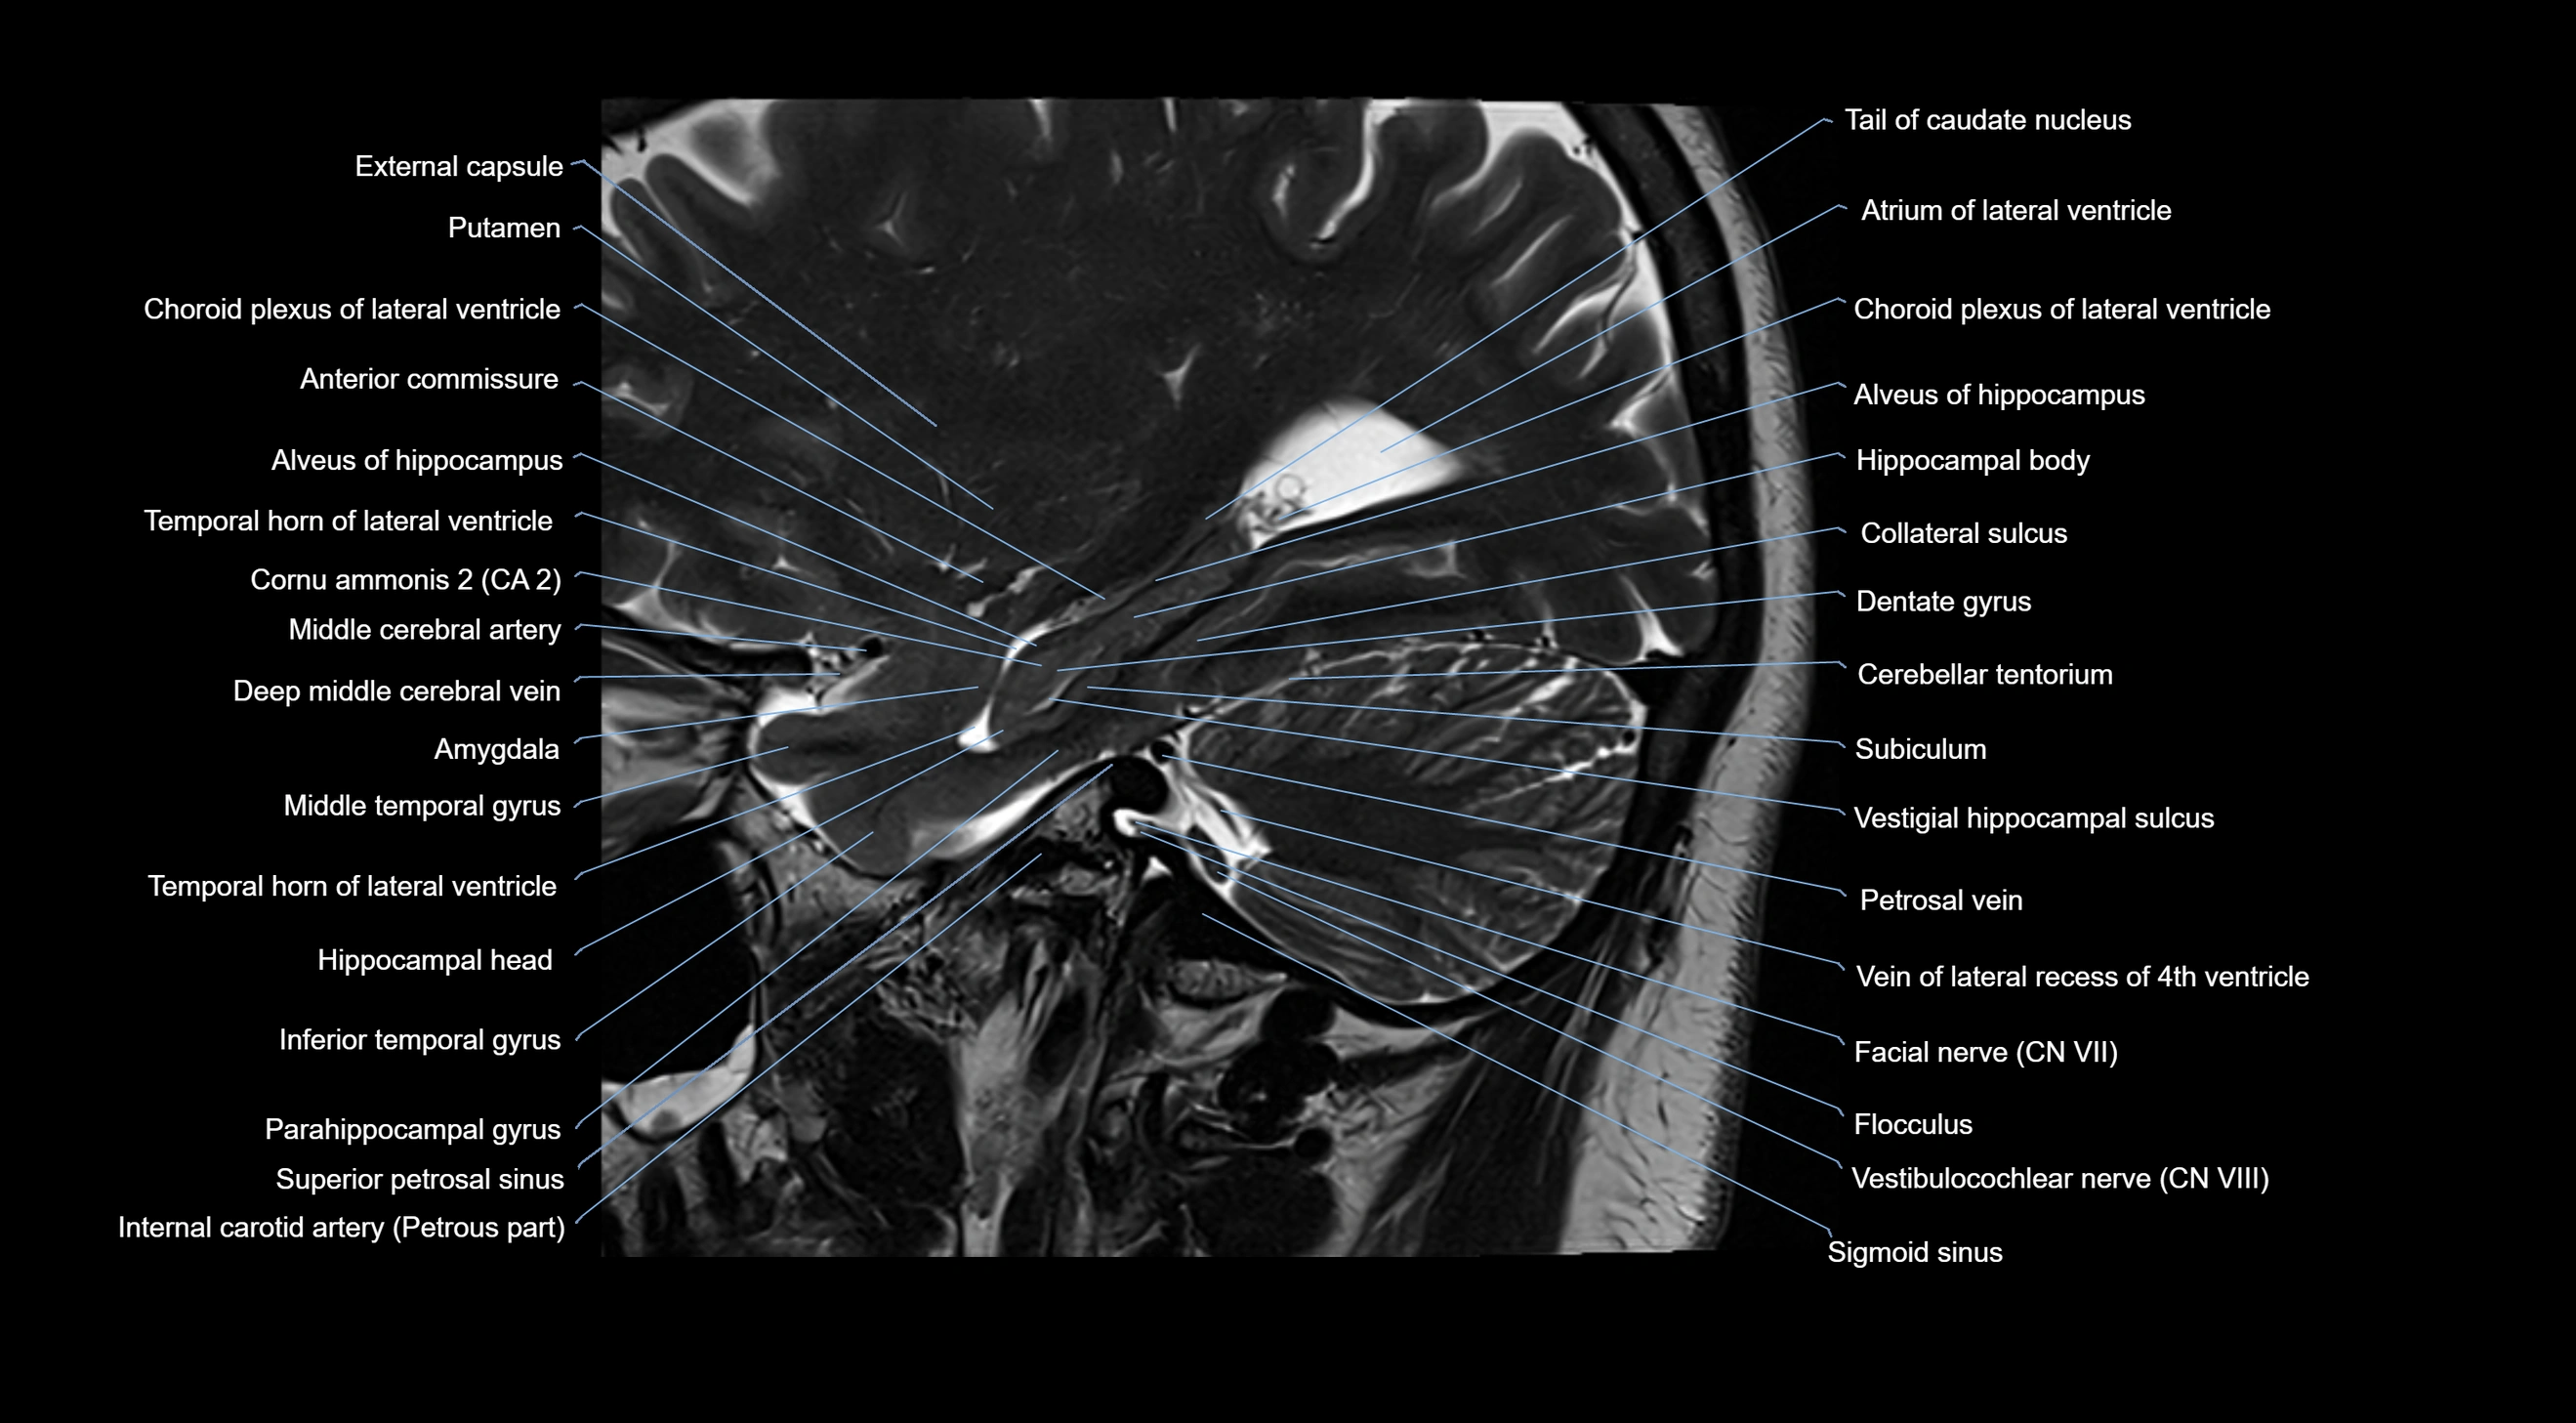

- Alveus

- Amygdala

- Anterior commissure

- Atrium of lateral ventricle

- Cerebellar tentorium

- Choroid plexus

- Choroid plexus of the lateral ventricle

- Flocculus

- Petrosal vein

- Sigmoid sinus

- Superior petrosal sinus

- Tail of caudate nucleus

- Temporal horn of lateral ventricle

- Vein of lateral recess of fourth ventricle

- Vestibulocochlear nerve (Cranial nerve VIII)